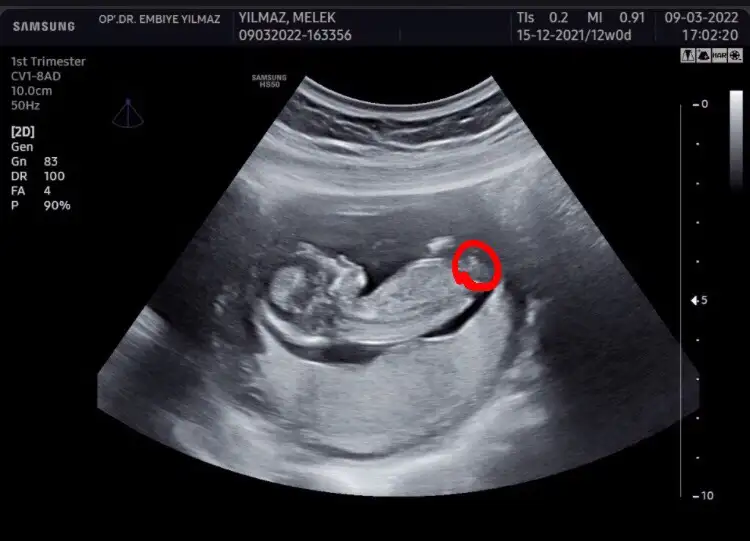

Ben bişey anlayamadım nuba göre benim ne oluyor acabaCumartesi cinsiyet öğreneceğim o yüzden bütün teorileri araştırırken bu karşıma çıktı bana mantıklı geldi gibişöyle ki omurgadan popoya doğru giden çizgi sonda yukarı doğru çıkıyorsa erkek, düz gidiyorsa kız oluyormuş fotoğraf ekleyeceğim orda daha ayrıntılı gösteriyor

Dr da öyle dedi emin olamadı alttan bakınca da kıza benziyor dediAyy maşallah ne güzel çıkmışsanki şu işaretlediğim yerde yukarı doğru bir çıkıntı varmış gibi geldi bana Öyle olunca da erkek deniyor ama bilemiyorum tamamen benim yorumum